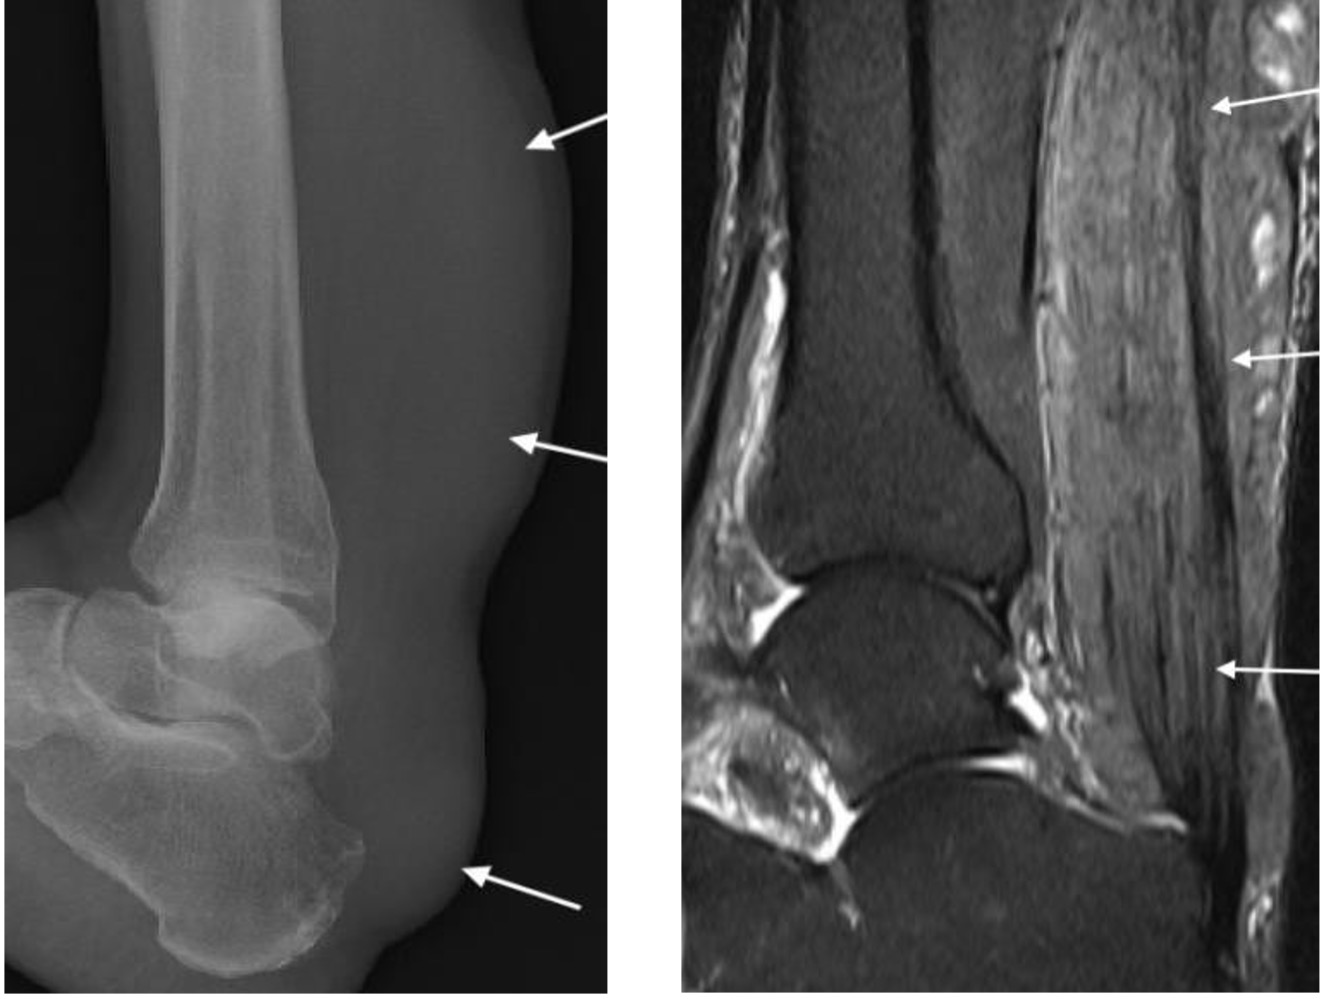

Pigmented villonodular synovitis

- More recently called intra-articular tenosynovial giant cell tumour

- Most commonly seen in young adults

- Characterized by villous nodular proliferation of the synovium with haemosiderin deposition

- Dense periarticular soft tissue swelling with pressure erosion of the subarticular bone

- Joint space preserved until fairly late

- No calcification

- MRI useful to demonstrate the villous nodular synovial masses with low signal haemosiderin on all imaging sequences

PVNS with periarticular soft tissue swelling (arrowheads), bone erosion (arrow) and low signal synovial proliferation on MRI (arrows)